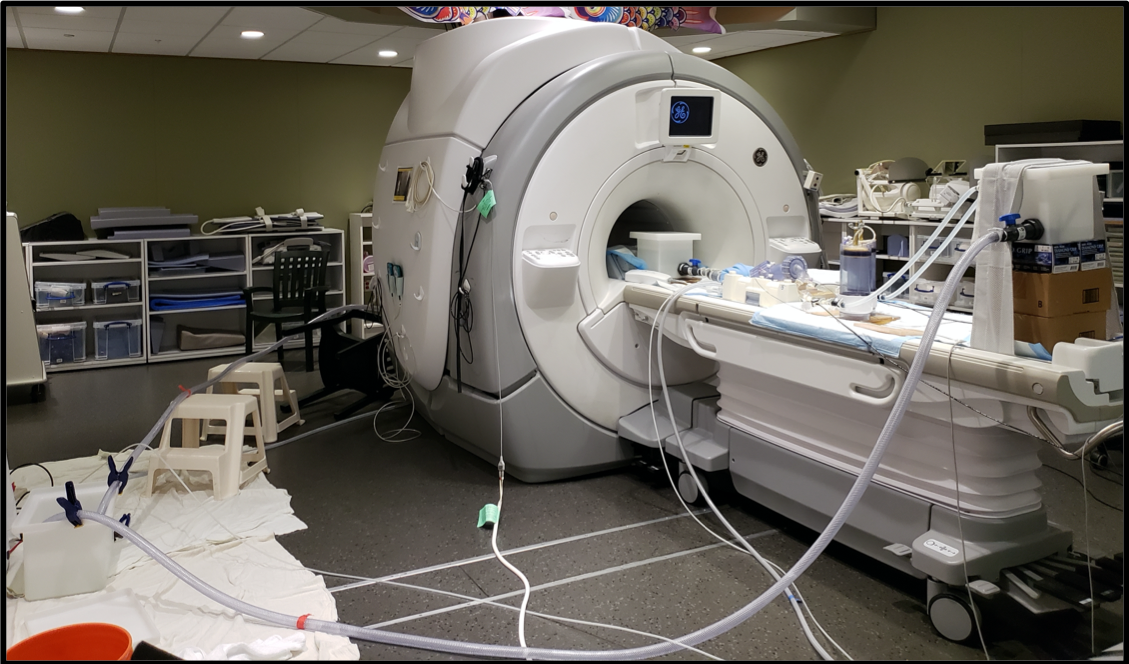

The experimental data in this study were obtained using the 4D flow MRI sequence developed by Markl et al. [28], which produced full 3D, three component, phase-averaged velocity fields in a physical model of the right ventricular outflow tract (RVOT) and pulmonary arteries. The experiments were performed in a whole body, 3 Tesla General Electric MRI scanner at the Richard M. Lucas Center for Imaging at Stanford University (Figure 1), and these data were discussed in a previous publication [39]. The gating signal for the 4D flow sequence was provided by the data acquisition system that was also used to control the ventricle pump. The cardiac cycle duration was 0.8325 s or approximately 72 beats per minute. Based on a retrospective gating scheme, the velocity data were acquired with a temporal resolution of approximately 83 ms, providing 10 time phases for the final data. The velocity at a point in the flow domain for a given phase represents the mean velocity during the time interval of that phase. Therefore, the velocity for each phase represents the phase-average of the velocity during an 83 ms interval during the cardiac cycle. This phase average is constructed from the flow fields of over hundreds of cardiac cycles and is therefore expected to smooth out small variations between cycles. The 4D flow MRI scans used 0.9 mm thick sagittal slices and spatial resolutions of 0.894 mm and 0.897 mm in the coronal and axial directions, respectively.

We developed an in vitro flow loop experimental setup that replicates physiological conditions over the cardiac cycle for the pediatric pulmonary system (Figure 3). The pulsatile flow loop was driven by a custom designed ventricle box that was inspired by pulsatile ventricular assist devices, such as the Berlin Heart EXCOR (The Woodlands, TX). A thin membrane in the ventricle box was pneumatically driven by a pulsatile air supply to create systole and diastole in the model and the working fluid. The digital trigger signal governing the pneumatic ventricle box was connected to the electrocardiogram (ECG) converter and trigger on the MRI system to signal the start of each cardiac cycle, allowing us to collect gated, phase-locked data.